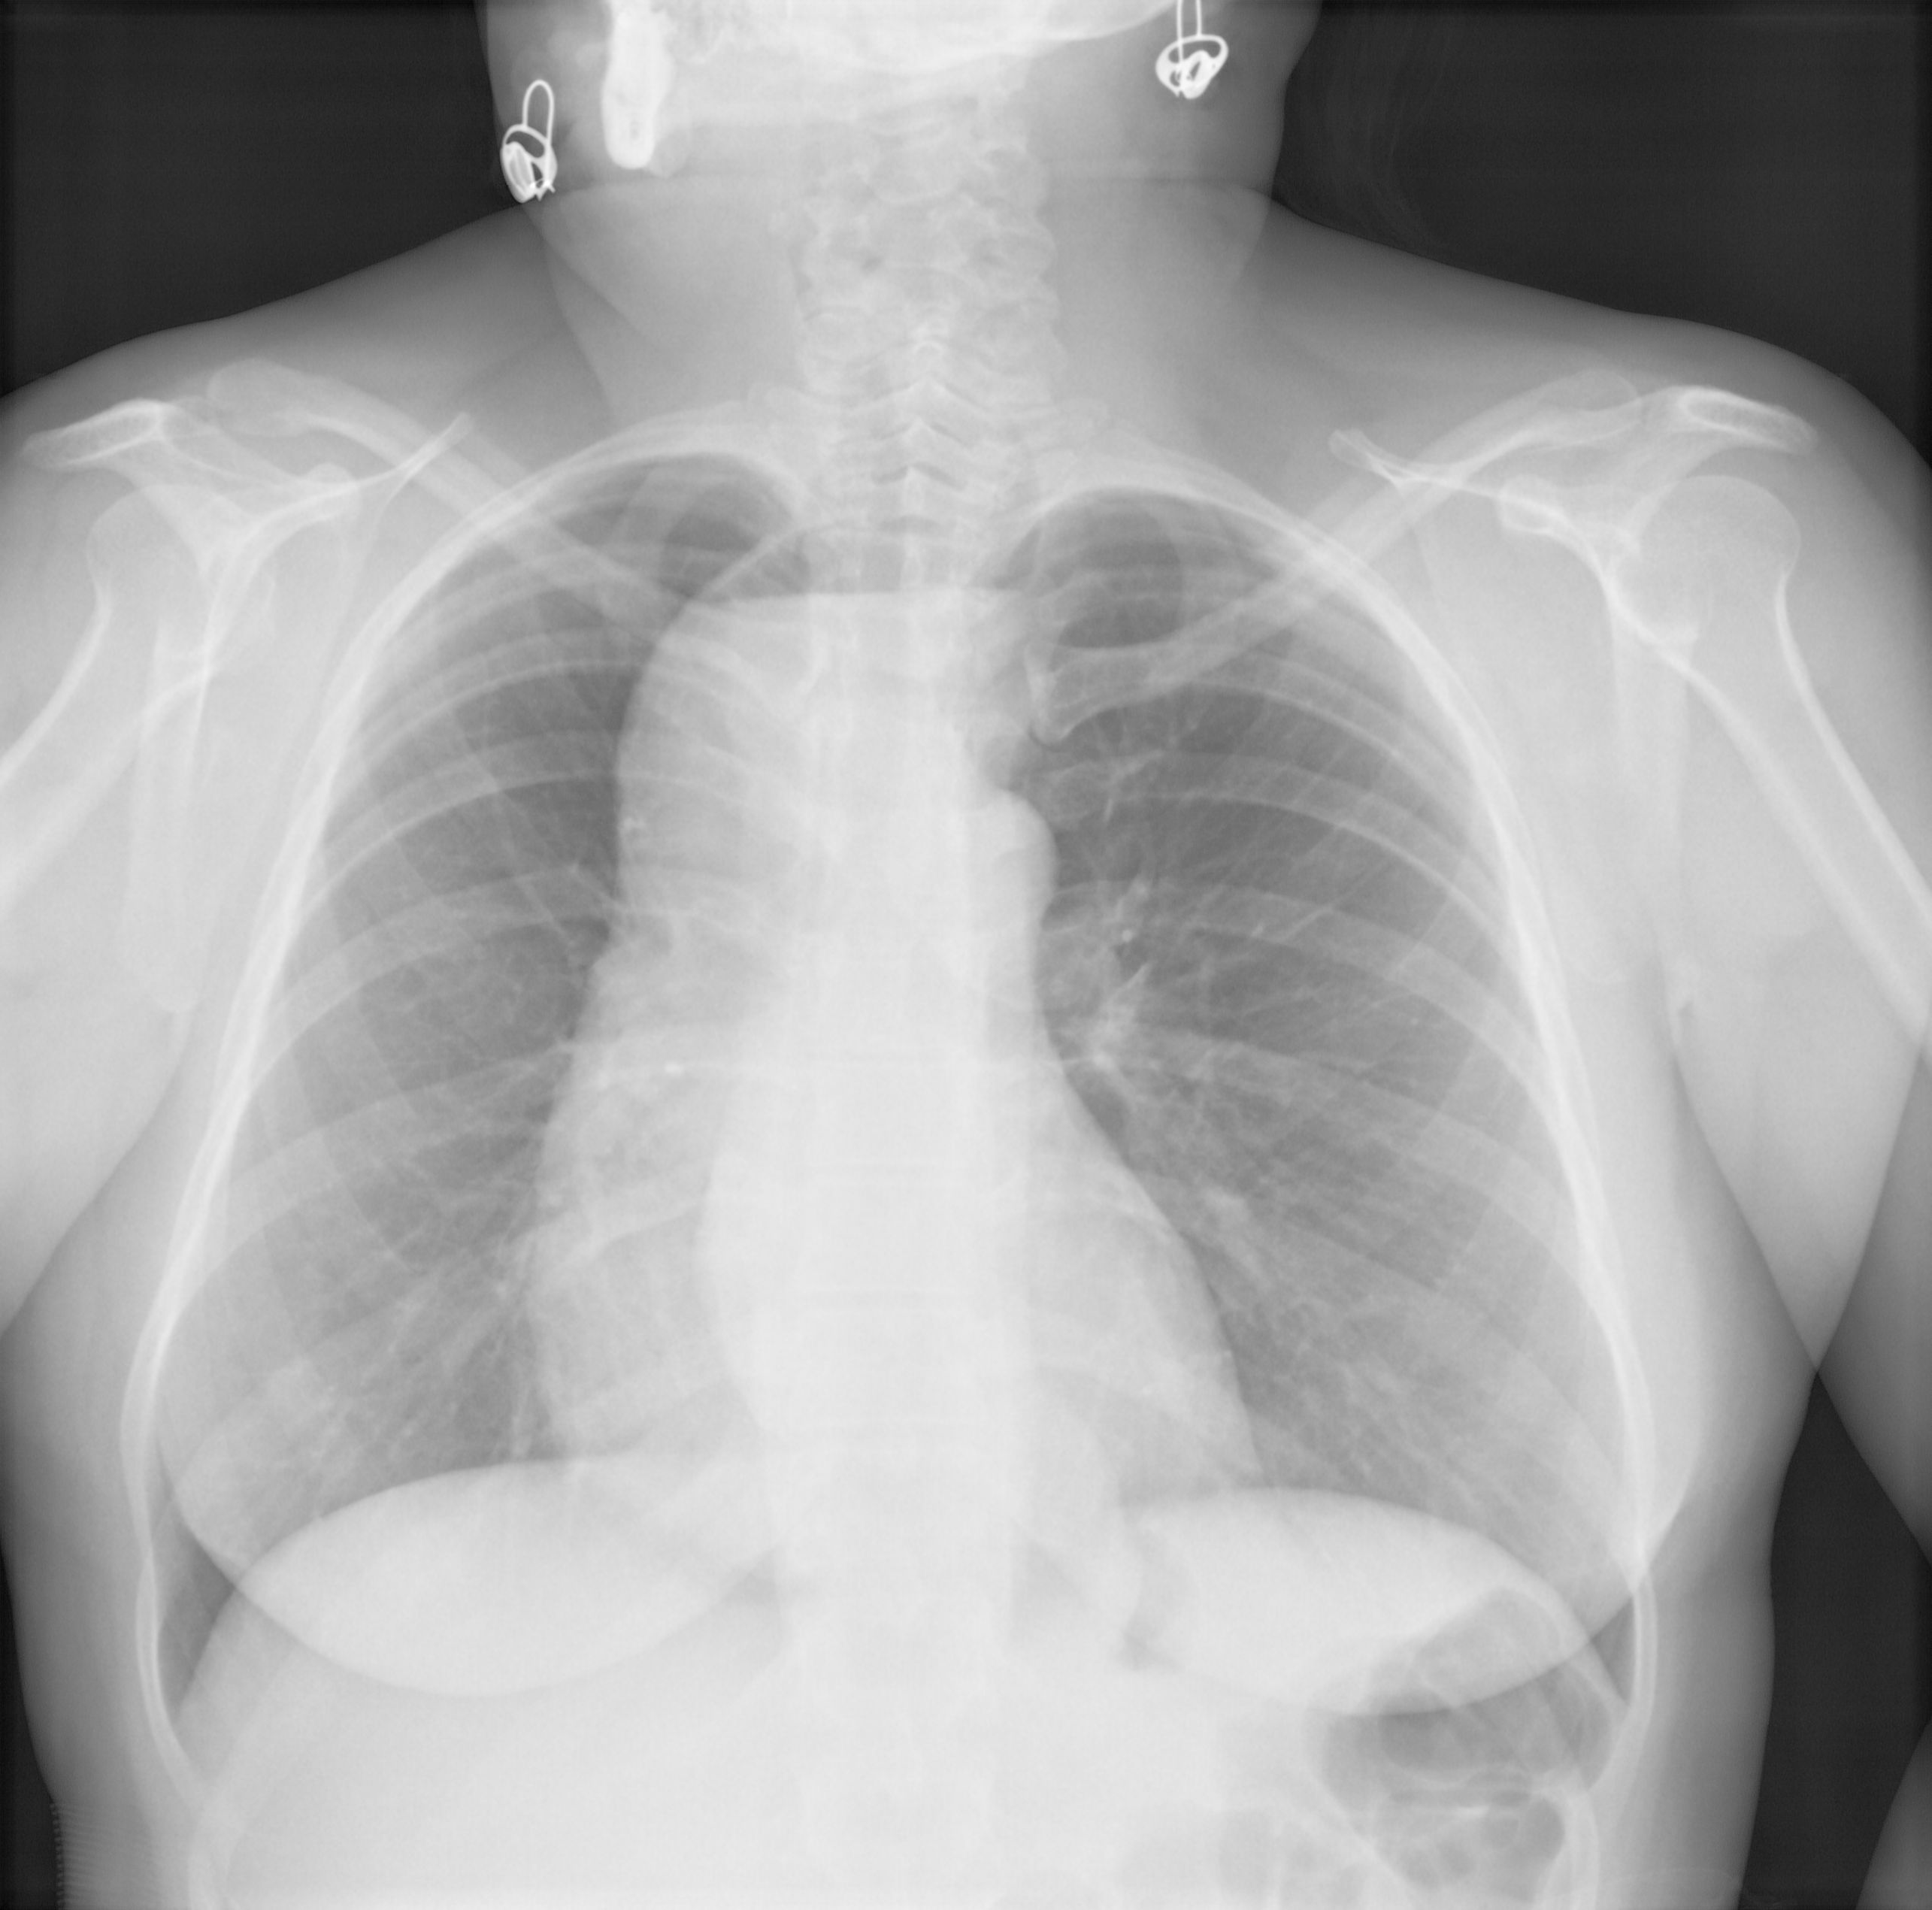

Ахалазия пищевода, даже уровень жидкости в пищеводе, верхнего этажа средостения.

Уровень просматривается, странно, что при всей картине отсутсвует какая- либо клиника.

Жалоб нет, попросил прислать и расспросить, отпишусь о результатах.

а еще шейное ребро слева.А вот ахалазию еще бы доказать не помешало ва-взвесью